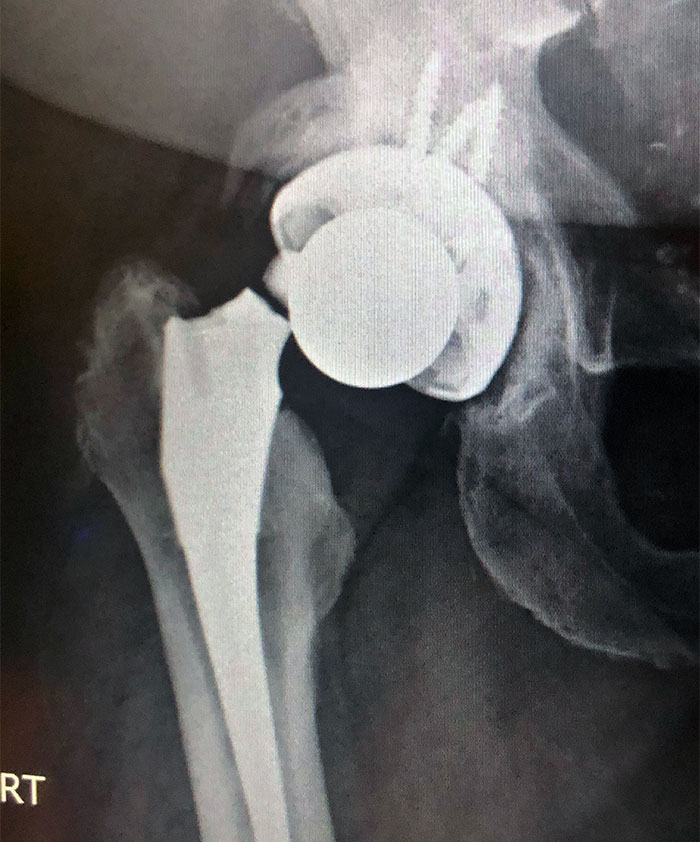

X-Ray Of My Metal Arm